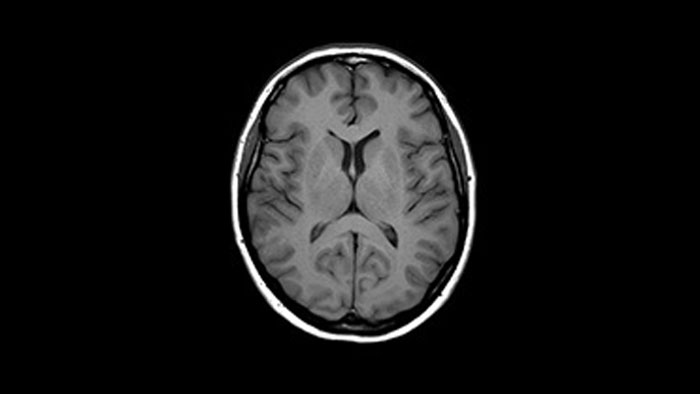

Brain overview